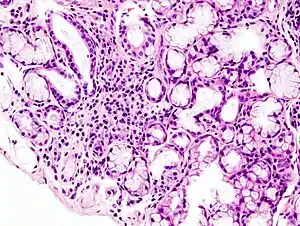

Image with a microscope of focal lymphoid infiltration in the minor salivary gland associated with Sjögren syndrome.

While the exact cause is unclear, it is believed to involve a combination of genetics and an environmental trigger such as exposure to a virus or bacteria.[4] It can occur independently of other health problems (primary Sjögren syndrome) or as a result of another connective tissue disorder (secondary Sjögren syndrome).[3] The inflammation that results progressively damages the glands.[7] Diagnosis is by biopsy of moisture-producing glands and blood tests looking for specific antibodies.[2] On biopsy there are typically lymphocytes within the glands.[2]

A lip/salivary gland biopsy takes a tissue sample that can reveal lymphocytes clustered around salivary glands, and damage to these glands from inflammation. This test involves removing a sample of tissue from a person’s inner lip/salivary gland and examining it under a microscope. In addition, a sialogram, a special X-ray test, is performed to see if any blockage is present in the salivary gland ducts (i.e. parotid duct) and the amount of saliva that flows into the mouth.[39]

A radiological procedure is available as a reliable and accurate test for SS. A contrast agent is injected into the parotid duct, which opens from the cheek into the vestibule of the mouth opposite the neck of the upper second molar tooth. Histopathology studies should show focal lymphocytic sialadenitis. Objective evidence of salivary gland involvement is tested through ultrasound examinations, the level of unstimulated whole salivary flow, a parotid sialography or salivary scintigraphy, and autoantibodies against Ro (SSA) and/or La (SSB) antigens.